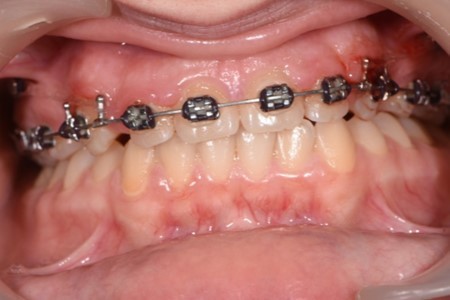

The working stage of the treatment was done with the use of a rectangular stainless steel archwire 0.019”x0.025” (Figure 5, Figure 6). Bodily movement was obtained and a minor intrusion. The incisal edges were displaced backward in order to provide a better incisal display at rest and during the smile. Unlike palatal arches, where the retraction is done by tipping the incisors, the mini implants in our case were able to provide a bodily retraction of the upper anterior teeth. Therefore, retraction was obtained with no anchorage loss. The improvement in the overjet and overbite was good.

Figure 6.Significant overjet and overbite improvement after implant based orthodontic retraction.

The labial inclination of the incisors was corrected and better torque values were obtained. With the use of the temporary anchorage devices, a total of 7 mm of retraction was done in this case.

By moving the incisal edges backward, the upper lip position in regard to the upper frontal teeth was modified. The new position of upper teeth will play a major role in maintaining stability and preventing relapse. A more stable contact was obtained between the incisal edges of the lower anterior teeth and the palatal surface of the upper frontal teeth.